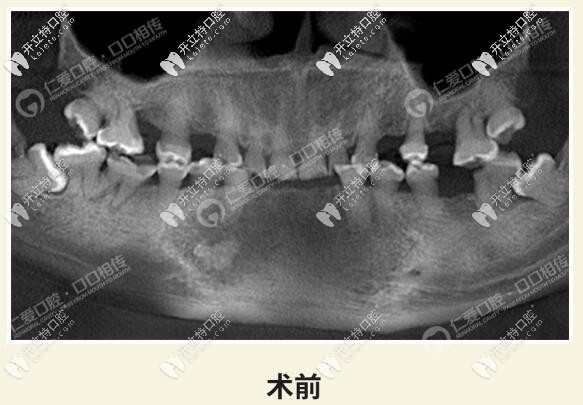

牙齒磨耗到底可不可怕?看看武漢這位趙先生,全口牙都被磨的全是爛牙,在口腔做了28顆全瓷冠修復(fù)。

而這位顧客整口牙全牙列均過(guò)度磨耗,經(jīng)過(guò)我院種植醫(yī)生全面檢查分析,判斷咬合垂直距離,采用了全冠修復(fù)。